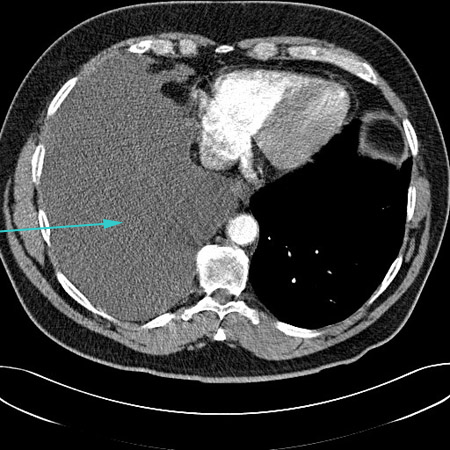

CT scan showing large right pleural effusion

From the collection of Dr Nicholas Maskell; used with permission